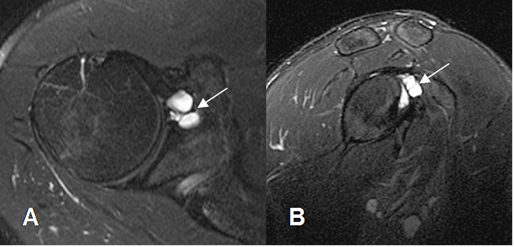

Fig 79. Quiste paralabral.

A: RM axial en STIR y B: RM sagital en STIR. Imagen ovalada y de consistencia líquida, en la parte anterosuperior de la glenoides, que corresponde a quiste paralabral.